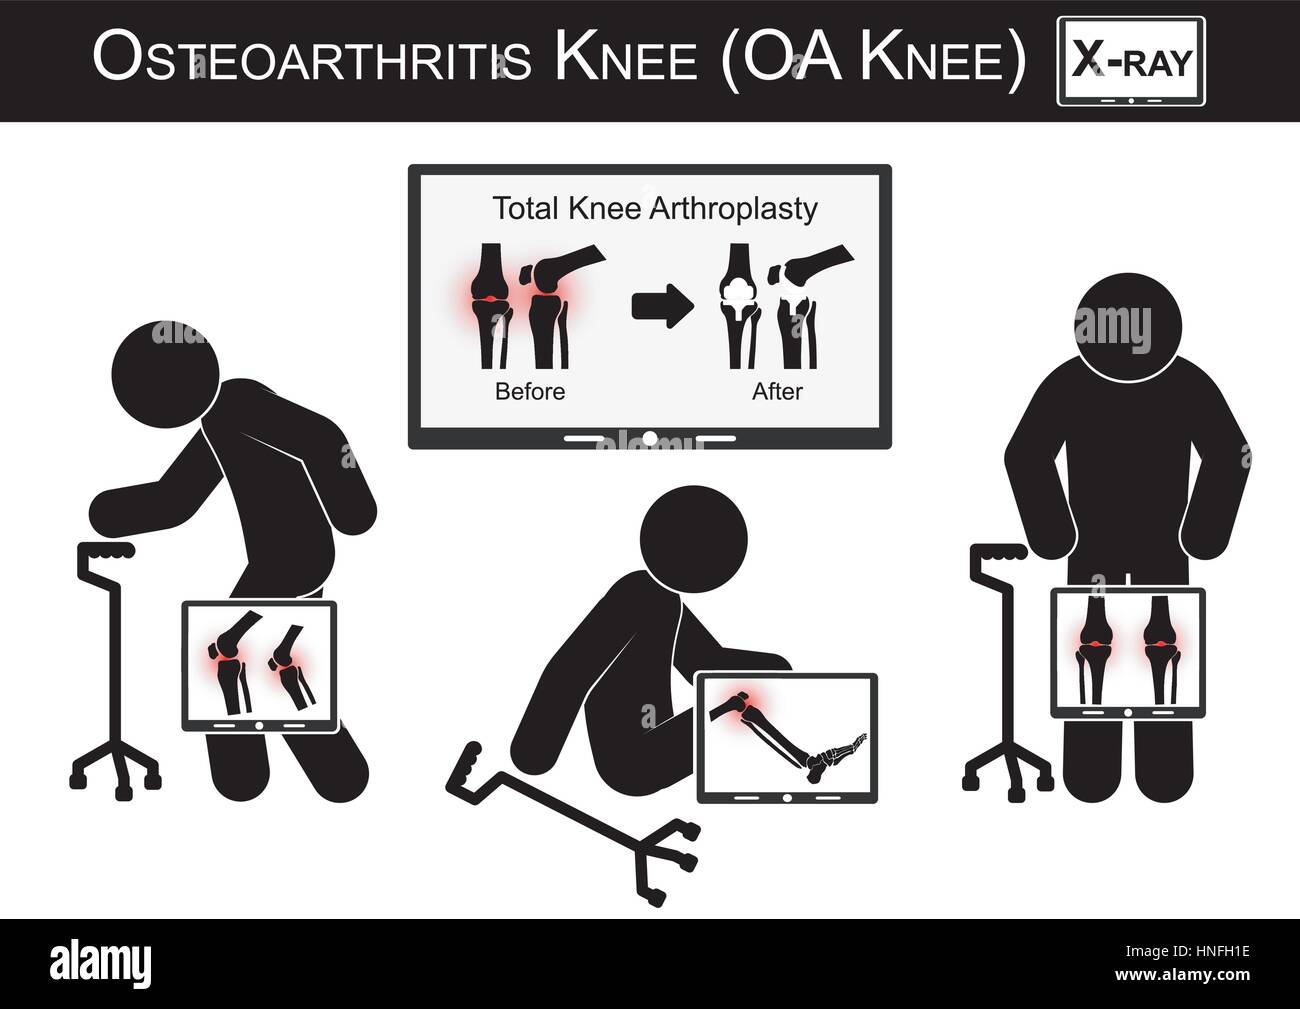

Vieil homme la douleur à son genou , Moniteur show image d'arthroplastie totale du genou ( avant et après traitement chirurgical de l'arthrose ) Banque D'Imageshttps://www.alamyimages.fr/image-license-details/?v=1https://www.alamyimages.fr/photo-image-vieil-homme-la-douleur-a-son-genou-moniteur-show-image-d-arthroplastie-totale-du-genou-avant-et-apres-traitement-chirurgical-de-l-arthrose-83327512.html

Vieil homme la douleur à son genou , Moniteur show image d'arthroplastie totale du genou ( avant et après traitement chirurgical de l'arthrose ) Banque D'Imageshttps://www.alamyimages.fr/image-license-details/?v=1https://www.alamyimages.fr/photo-image-vieil-homme-la-douleur-a-son-genou-moniteur-show-image-d-arthroplastie-totale-du-genou-avant-et-apres-traitement-chirurgical-de-l-arthrose-83327512.htmlRMERFW2G–Vieil homme la douleur à son genou , Moniteur show image d'arthroplastie totale du genou ( avant et après traitement chirurgical de l'arthrose )

Vieil homme la douleur à son genou , Moniteur show image d'arthroplastie totale du genou ( avant et après traitement chirurgical ) arthrose vector ( télévision des Illustration de Vecteurhttps://www.alamyimages.fr/image-license-details/?v=1https://www.alamyimages.fr/photo-image-vieil-homme-la-douleur-a-son-genou-moniteur-show-image-d-arthroplastie-totale-du-genou-avant-et-apres-traitement-chirurgical-arthrose-vector-television-des-133723002.html

Vieil homme la douleur à son genou , Moniteur show image d'arthroplastie totale du genou ( avant et après traitement chirurgical ) arthrose vector ( télévision des Illustration de Vecteurhttps://www.alamyimages.fr/image-license-details/?v=1https://www.alamyimages.fr/photo-image-vieil-homme-la-douleur-a-son-genou-moniteur-show-image-d-arthroplastie-totale-du-genou-avant-et-apres-traitement-chirurgical-arthrose-vector-television-des-133723002.htmlRFHNFH1E–Vieil homme la douleur à son genou , Moniteur show image d'arthroplastie totale du genou ( avant et après traitement chirurgical ) arthrose vector ( télévision des